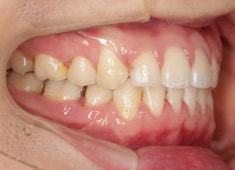

症例紹介

先天欠如歯両側上顎3番

治療法:フルパッシブブラケット:T21

治療前